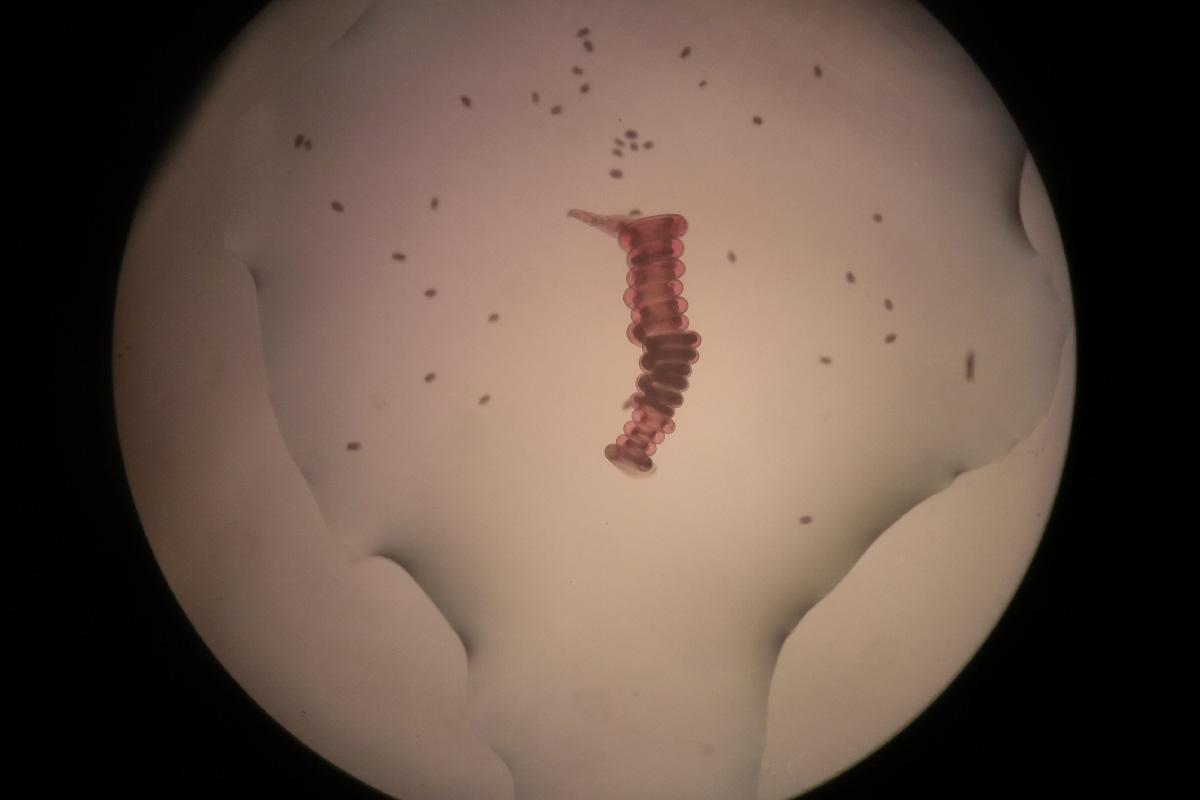

In a study published on Friday, researchers at Rutgers University have found that a molecule released by an intestinal parasite promotes wound healing in mice.

“We have developed a novel therapy for the treatment of skin wounds that favors regenerative wound healing over … scarring,” William Gause, director of the Center for Immunity and Inflammation at Rutgers University and the study’s lead author, said in the press release.